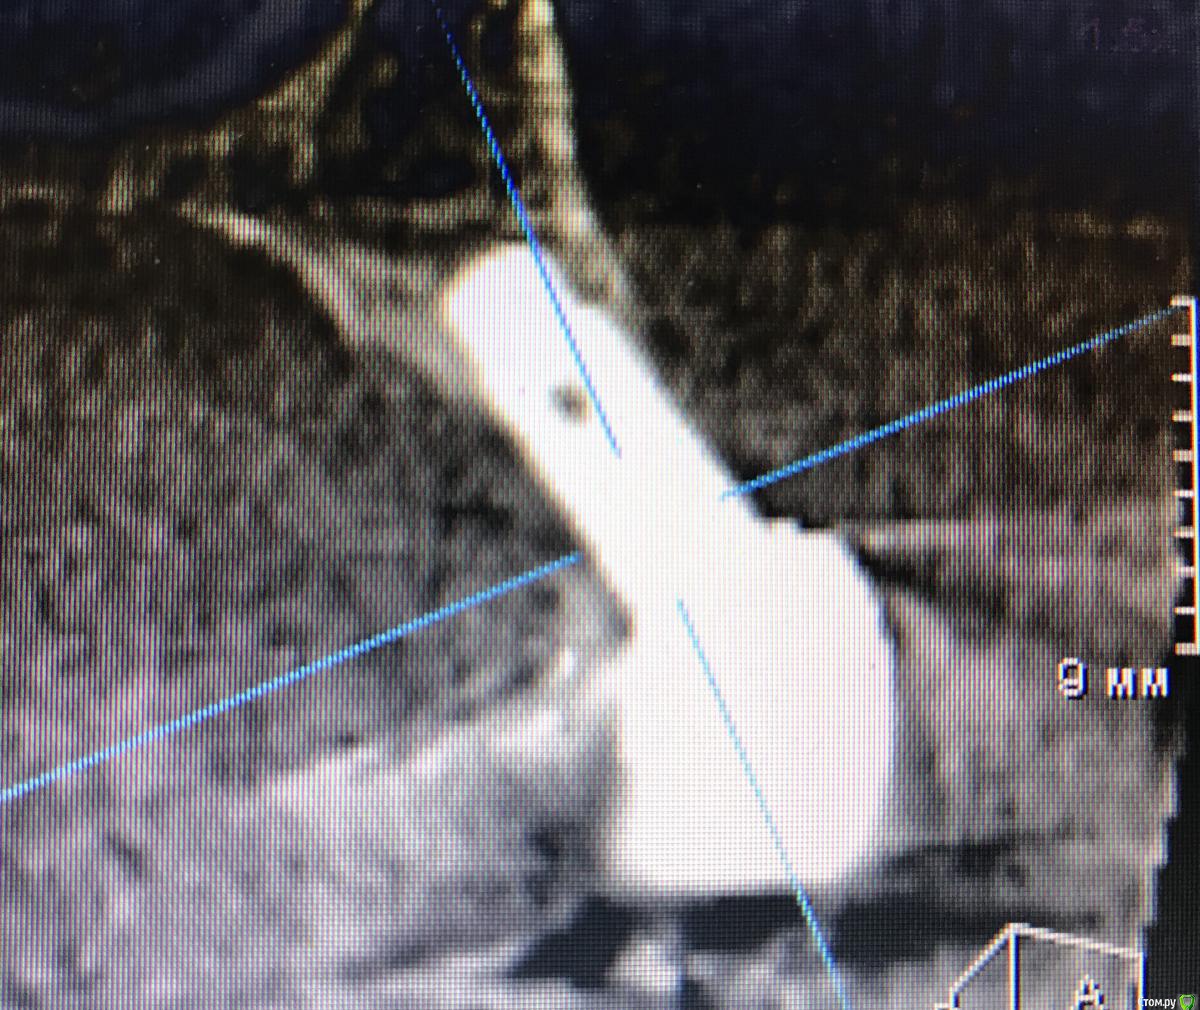

DenisV Опубликовано 21 марта, 2018 Поделиться Опубликовано 21 марта, 2018 Уважаемые коллеги планируется удаление и установка имплантата 3.8 10 dentium можно ли будет обойтись без костной и тканевой аугментации? Ссылка на комментарий

DenisV Опубликовано 21 марта, 2018 Автор Поделиться Опубликовано 21 марта, 2018 Уважаемые коллеги планируется удаление и установка имплантата 3.8 10 dentium можно ли будет обойтись без костной и тканевой аугментации? Ссылка на комментарий